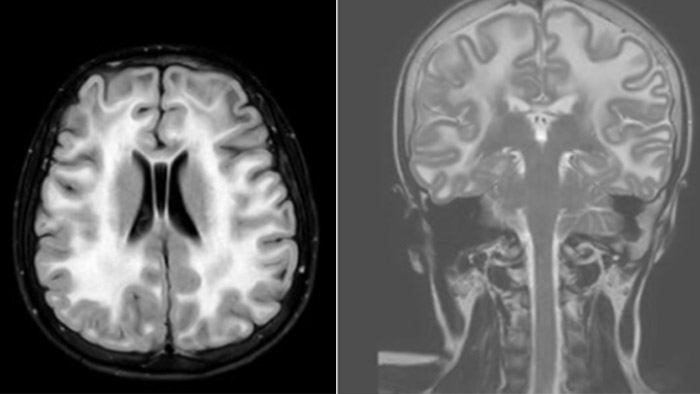

Hydrocephalus post hemorrhagic

Both pictures show a ventriculoperitoneal shunt. With our previous scanner our hydrocephalus protocol needed about 25 min. With Ambition the examination time is about 14 min. including a CSF PCA sequence to show flow in the aqueduct.